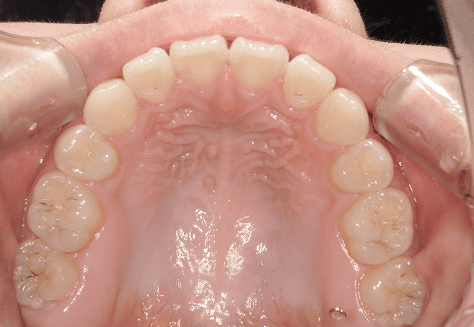

S.K

治療前

治療後

主訴

歯が重なっていて気になる。前歯が出ていて唇が閉じにくい。ハミガキがしにくい。

診断

上顎前突・叢生

年齢/性別

20代/男性

抜歯部位

上下第三大臼歯

使用装置

上下インビザライン

保定装置

上下ビベラリテーナー

料金

初回資料採得・・・・・・・30,000円

診断料・・・・・・・・・・33,000円

動的治療終了時資料採得・・5,500円 -

基本料金

990,000円

診察料金

1,100円×33回

治療期間

3年5カ月